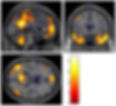

Figure 1. An fMRI brain scan looking at activation in the brain of a person with the Fragile X Premutation (research by Stephanie Brown and Andrew Stanfield)

Functional brain imaging research has shown that carriers of the premutation, both with and without FXTAS, also have some changes in their brain activation patterns in response to certain tasks carried out in the scanner compared to people without the premutation.

In memory tasks, carriers with and without FXTAS performed equally in comparison to comparison volunteers without the premutation, however carriers exhibited decreased brain activation in specific regions of the frontal cortex. The frontal cortex is an area which is important for decision-making, attention and short-term memory. Additionally, premutation groups generally showed increased activation in the parietal lobe of the brain in response to these memory tasks. The parietal lobe is a region which controls perception and integration of sensory inputs to the brain, and higher activation in premutation carriers may mean that this area of the brain is working harder than normal when engaging memory and decision-making processes [11]. During numerical processing tasks, premutation carriers also generally showed lower fronto-parietal activations, although again performance was not significantly different in these tasks compared to the comparison group [12]. In social and emotional tasks performed in the scanner, premutation carriers showed less activation than comparison subjects in the limbic system, which is the emotional centre of the brain [13, 14]. This finding could possibly be linked to the increased likelihood of premutation carriers to develop social or mental health difficulties such as autism spectrum disorder, depression or anxiety throughout their life-span.